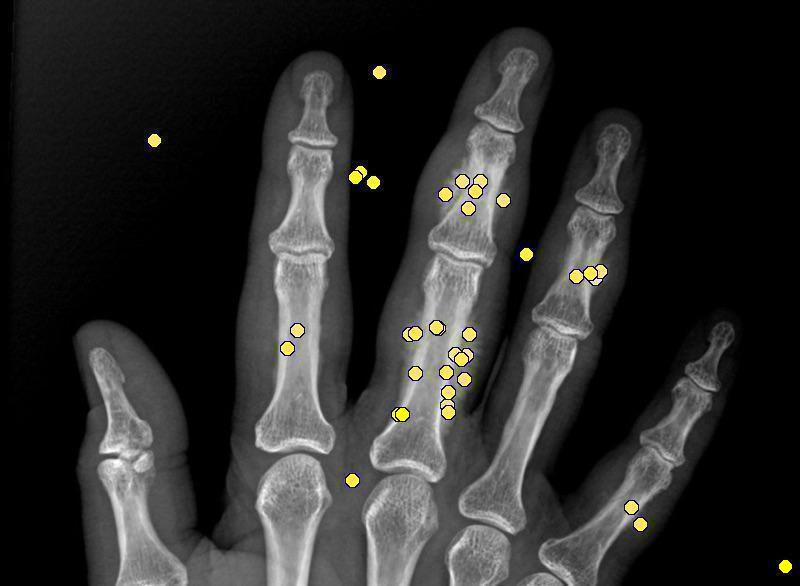

ACL test